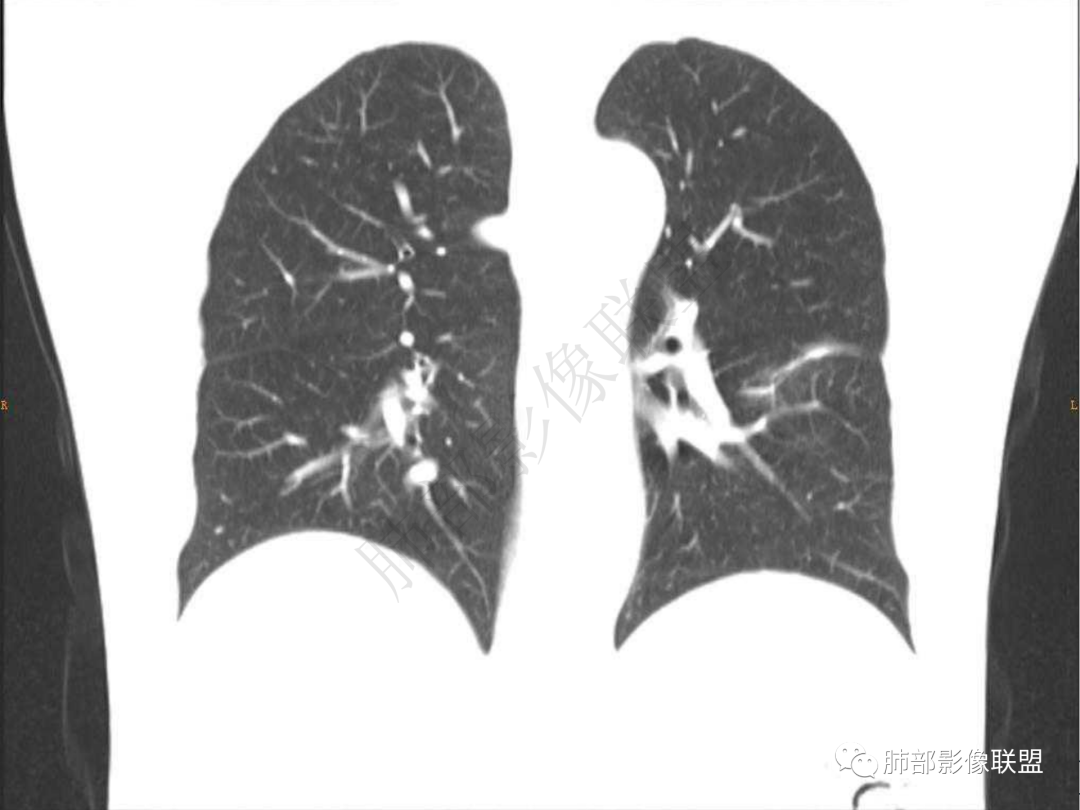

2.左肺下叶团片影,跨背段及内前基底段,实性部分类椭圆形,密度不甚均匀,可见毛刺及棘状突起,未见典型分叶及胸膜凹陷。病灶上下缘可见相应肺段支气管旁进侧出,管壁轻度增厚,未见狭窄阻塞。

3.周边较大范围磨玻璃影,边界相当模糊,小叶增厚明显。注意叶裂另一侧、左肺舌段亦可见磨玻璃影及增厚的小叶间隔。未见明确卫星病灶。

2.周围磨玻璃影边界不清缺乏限制,甚至“激惹”到相邻肺叶,也许提示较明显的炎性水肿。